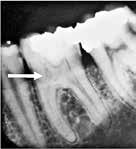

Fig. 11. A. Skematisk illustration af tand med pulpasten i pulpakammer og rodkanaler, hvilket kan gøre det vanskeligt at lokalisere kanalindgangene og udrense kanalerne (18). B. Bitewing-optagelse viser generaliseret dannelse af pulpasten i molarerne (pile). C. Periapikal optagelse af -6 med omfattende forkalkninger i pulpakammer og rodkanaler (pil).

Fig. 11. A. Schematic illustration showing tooth with pulp stone in the chamber and root canals creating potential difficulty in locating root canal orifices and instrumentation (18). B. Bitewing radiograph showing generalized pulp stone formation on molars (arrows). C. Periapical radiograph of mandibular left first molar with extensive calcifications in the pulp chamber and root canals (arrow).

Radiologiske fund

Forekomst af pulpasten i pulpakammeret kan blokere kanalindgangene, og der er derfor behov for forstørrelse for at kunne lokalisere kanalindgangene (Kategori B) (Fig. 11A-C). En kanal, der er meget snæver, kræver betydelige tekniske færdigheder under udrensning til korrekt rodmål (Kategori C).